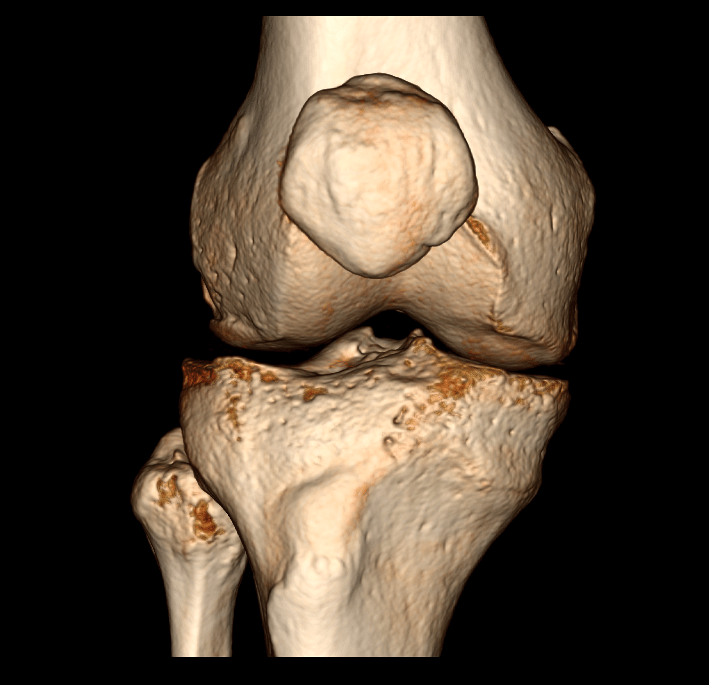

São indicações para a realização de TC do joelho a dor, edema (inchaço) ou impotência funcional (“falhas”) do joelho. Um dos exemplos de patologias avaliadas nesse procedimento é a artrose do joelho (gonartrose), que corresponde ao desgaste da articulação, frequente em doentes com idade mais avançada.

A tomografia em questão é o exame que analisa a articulação do joelho e os ossos, como fêmur, tíbia, patela e fíbula.